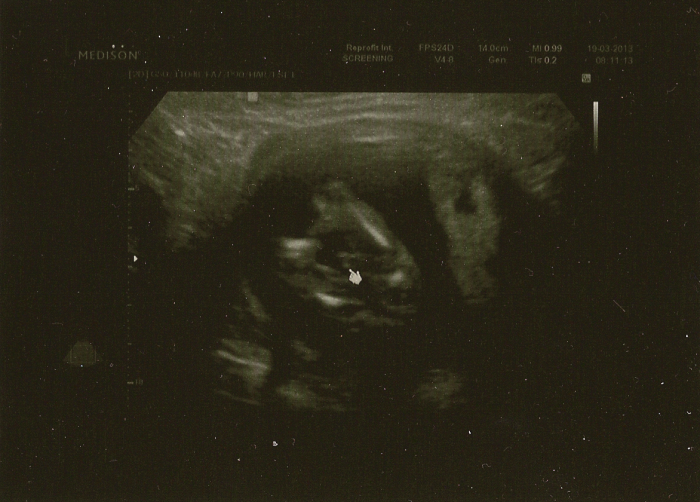

chlapeček se potvrdil,dokonce mame fotku jeho pindíka

a takhle už vypadame,bude to fešák

ivet gratulace ke chlapeckovi,ale priznam se,ze na fotce nevidim a nepoznam vubec nic

ve kterym jsi mesici-tydnu,ze se uz poznalo pohlavi? ach jo at koukam jak koukam ja na ty fotce nepoznam ani kde je hlava natoz tam u Tebe videt,ze je to kluk

[301634] Maku - ja to vzdavam i kdyz to tam je vyznacene sipkou pokud to dobre chapu,ale i tak jsem z toho jelen

Jo a na fotečce jsem pindíka nenašla teda, tak mě zkus nasměrovat. Hlavičku a páteř vidím, ale pak mi to nějak všechno splývá

Dento, je tam ten kurzor, tak tam je videt pindik a pytlik, je to pohled jakoby od zadecku, po stranach jsou nohy

Jani pokud jsem dobre u Ivet videla, tak kdyz se nasmerujes podle zadecku tak na konci briska je takova svetlejsi smouha, tak pokud se nepletu, tak to by melo bejt ono

Dendo dekuju za gratulace,na tyhle fotce bych pohlavi taky nepoznala ale mam jeste podobnou fotku jako maku kde je videt pindik

na tyhle fotce je dole hlavicka a smerem nahoru je videt pater,telicko...neboj pak budes vedet az ti to doktor popise tak si na te fotce to svoje miminko najdes

ted jsem v 18tt ale vime to uz od 13tt tak ti drzim palecky at se brzo taky dockas